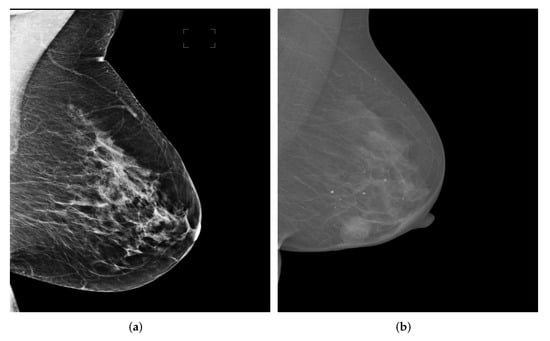

In Figure 9, we show two examples from the two datasets for intuitive interpretation. As can be seen, breast regions only appear in the top left corner while there is a large margin on the right hand size of the images. Therefore, the pre-processing procedure is meaningful to extract breast-only regions from the images and reduces potential overall computational cost. As for the image contrast between pectoral muscle and breast region, the mammography image from OPTIMAM dataset has better contrast as it shows a salient boundary between pectoral muscle and breast while the pixel intensities of the pectoral muscle area and breast area in images from INBreast seem to be more homogeneous.

We can see from Figure 11a that the lower part of the pectoral muscle has a very weak boundary between it and the breast region, which could be a challenging situation for traditional image segmentation methods. However, all Deeplabv3+ models successfully segmented the pectoral muscle while the InceptionResNetv2-based one performed best among all models in terms of all evaluation metrics except Sensitivity.

Figure 9. Mammography image examples from OPTIMAM and INbreast datasets. (a) An example image from OPTIMAM. (b) An example image from INBreast.